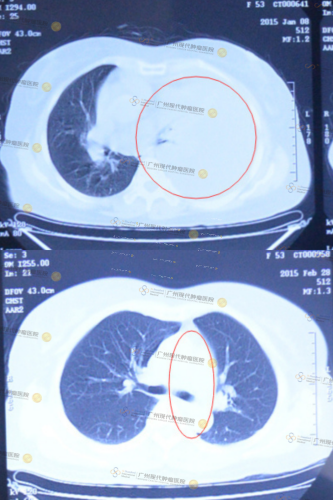

So sánh kết quả chụp CT trước và sau của cô Nghiêm Thị Thu